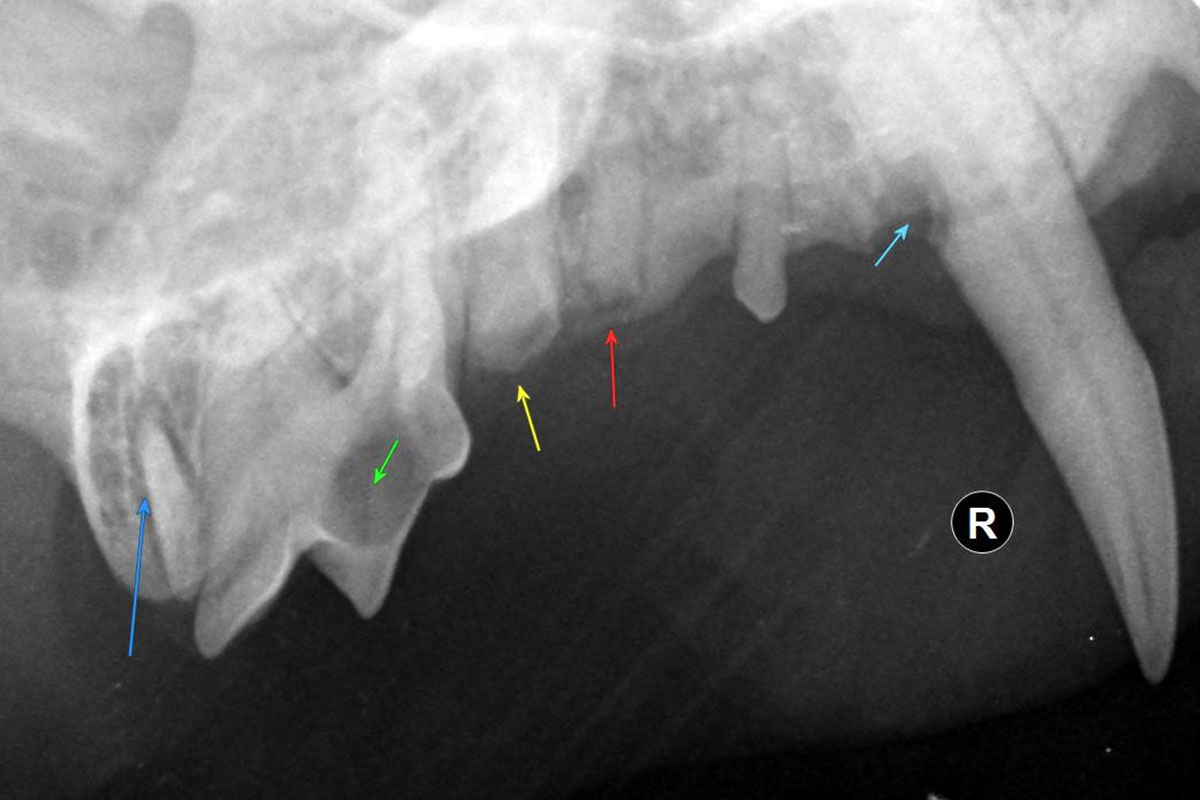

Zahnröntgen

Genau wie beim Menschen sind auch bei Tieren die Zähne wichtig für die Gesamtgesundheit. Zahnuntersuchungen mittels Röntgen sind daher heute Standard. Im Gegensatz zu einem herkömmlichen Röntgengerät ermöglicht uns ein spezielles Zahnröntgengerät überlagerungsfreie Aufnahmen, da es direkt in die Maulhöhle positioniert werden kann. Außerdem ist beim Zahnröntgen die Strahlenbelastung wesentlich geringer. In Spezialfällen wird ein einzelner problematischer Zahn abgelichtet, meist aber alle Zähne, damit sie inklusive Wurzeln genau begutachtet werden können. Dafür sind Speicherfolien in unterschiedlichen Größen vorhanden.